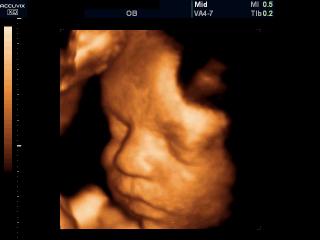

Лицо плода, 3D

Accuvix-XQ. Лицо плода, 3D.